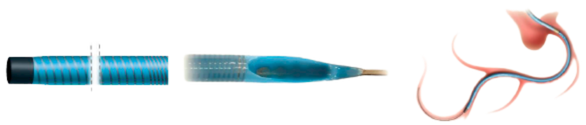

Flowguide

EXTEND THE REACH OF THE GUIDING CATHETER WITH REDUCED PRESSURE DAMPENING

The FlowGuide guide extension catheter reduces pressure dampening through 9 small perfusion openings in the distal shaft. A radiopaque soft tip for true distal end visibility facilitates precise device positioning. A stainless steel reinforcement embedded in the distal shaft ensures optimal lumen integrity and smooth device delivery. With a distal shaft length of 15 cm the FlowGuide is customized for optimal use in transradial procedures. The oval push rod guarantees no compromise with side along SDS delivery while securing optimal pushability.